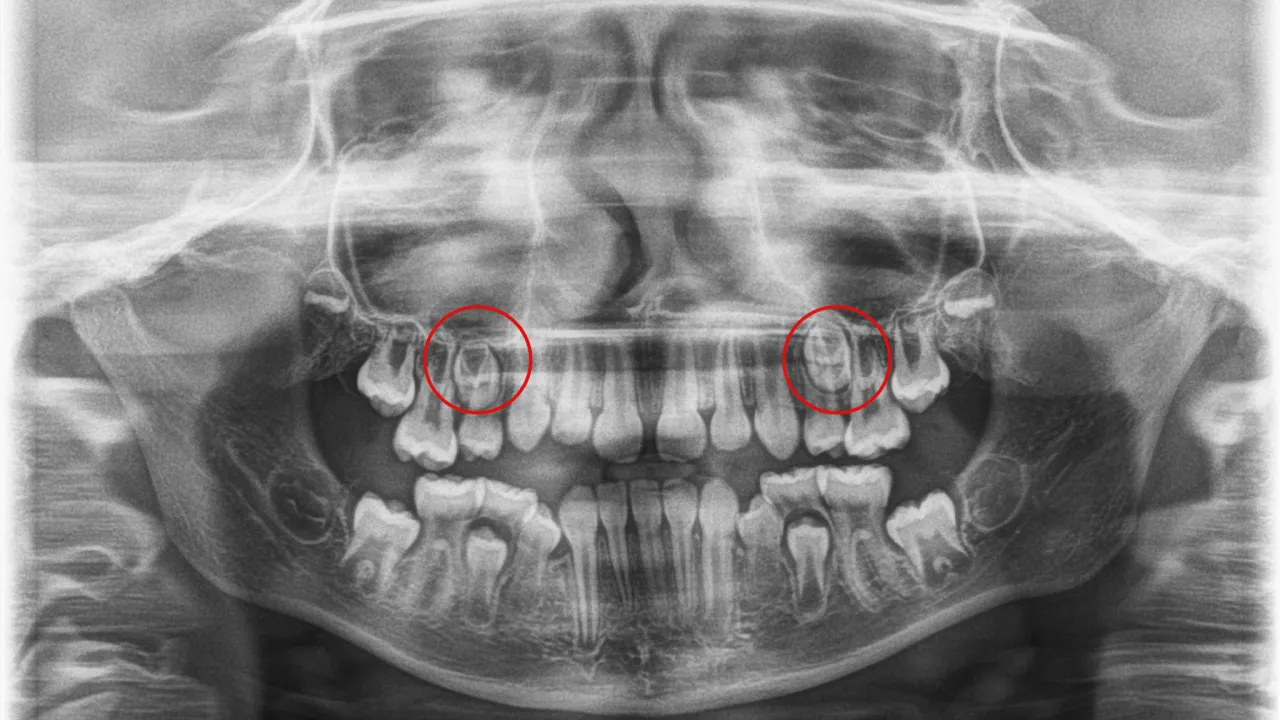

Resorpcja korzeni to proces skracania się korzeni zębów, który bywa powikłaniem leczenia ortodontycznego. Choć niewielka resorpcja występuje dość często i jest uznawana za normalne zjawisko adaptacyjne, w rzadkich, zaawansowanych przypadkach może ona znacznie osłabić ząb. Potencjalne przyczyny to stosowanie zbyt dużych sił, indywidualne czynniki genetyczne pacjenta lub bardzo długi czas leczenia.

Jako ortodonci, zawsze monitorujemy stan korzeni zębów podczas leczenia. Wykorzystujemy do tego celu zdjęcia rentgenowskie, które pozwalają nam ocenić, czy proces resorpcji nie postępuje w niepokojącym tempie i czy nie zagraża stabilności zębów. To jeden z kluczowych elementów kontroli bezpieczeństwa.

Warto pamiętać, że niewielkie skrócenie korzenia nie zawsze musi oznaczać problemy w przyszłości. Zęby z taką resorpcją mogą służyć pacjentowi przez wiele lat. Jednakże, zaawansowane przypadki resorpcji, gdzie korzeń jest znacznie skrócony, mogą znacznie zwiększyć ryzyko utraty zęba i wymagają szczególnej uwagi oraz ewentualnej modyfikacji planu leczenia.